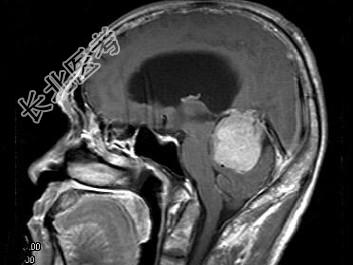

- 单项选择题男,61岁, 头晕头痛伴行走不稳1月余,根据所提供图像, 最可能的诊断是 ( )

A、胶质瘤

B、髓母细胞瘤

C、(天幕切迹缘)脑膜瘤

D、转移瘤

E、淋巴瘤